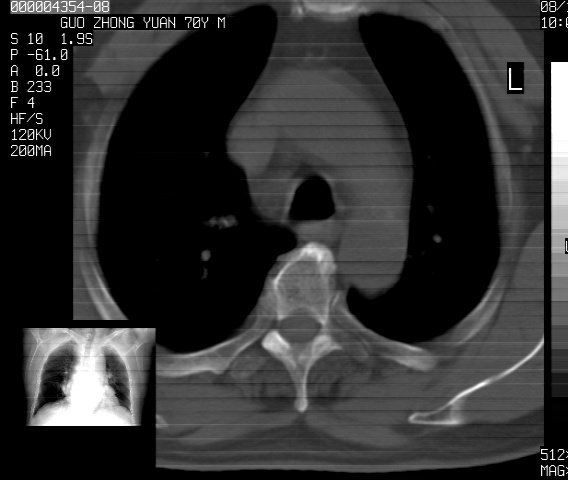

以下是引用sdzyy在2008-12-1 11:49:00的发言:[br]图像不全,请上传,右下肺炎症可能性大,占位待排.

以下是引用zjzjr在2008-12-1 14:53:00的发言:[br]图像不全,请上传,右下肺炎症可能性大,占位待排.心影增大,建议进一步检查.